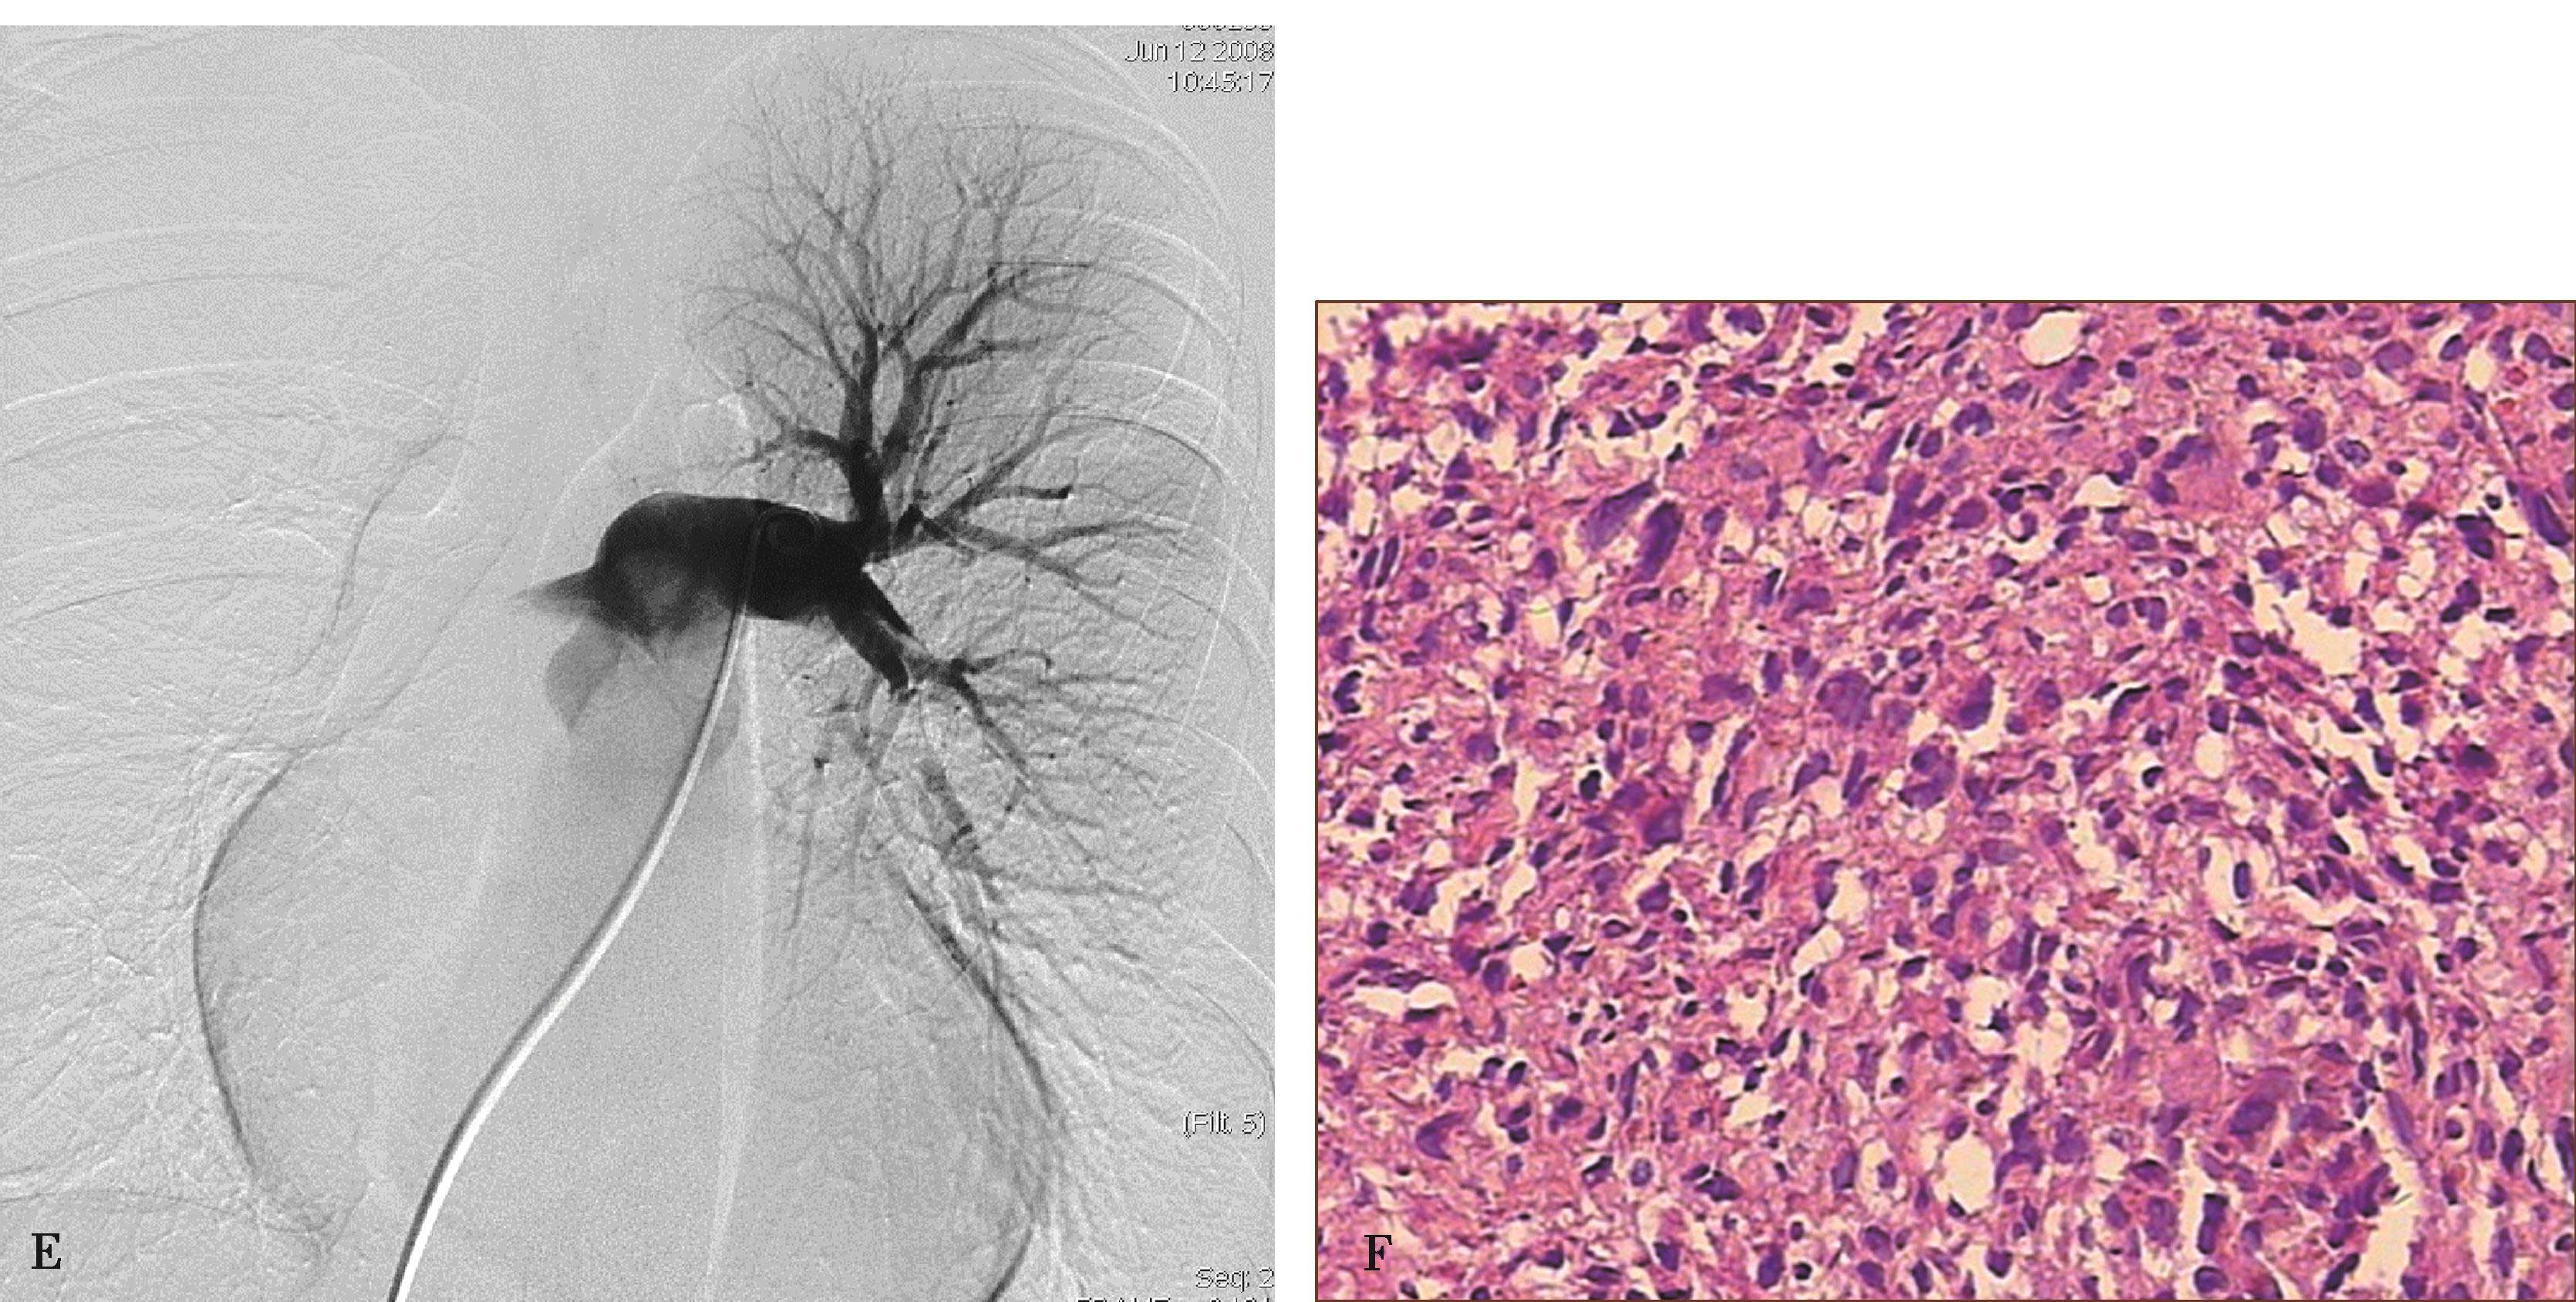

图8-5-6 坏死性肉芽肿性血管炎(韦格纳肉芽肿)

A.胸部X线片,两肺多发结节,不规则空洞形成(↑);B~D.横断图像,两上、下肺多发不规则结节肿块,大小不等,不规则空洞形成,壁薄厚不一,边缘不规则,液平形成;病理检查:E.肺小血管横断面,显示炎性细胞浸润累及部分血管;F.肺小血管纵切面,炎性细胞浸润,部分管壁破坏。CT诊断:韦格纳肉芽肿(病理证实为坏死性肉芽肿性血管炎)

2.坏死性肉芽肿性肺血管炎(韦格纳肉芽肿)

韦格纳肉芽肿(Wegener granulomatosis),又称坏死性肉芽肿性肺血管炎,有肉芽肿形成,累及小血管、静脉及毛细血管,也见累及中等血管。肺血管受累病理改变是肺(中)小动脉坏死性肉芽肿性血管炎。临床常以上呼吸道为首发症状,如鼻窦炎、鼻腔、气管慢性炎症。胸部X线片示双肺多发性斑片状、结节及空洞影,主要分布两肺中下野,多发性/多样性为其特点,确诊需肺活检。

(1)坏死性肉芽肿性肺血管炎CT征象及诊断:

高分辨率CT(平扫)对诊断有重要价值。显示肺实质多发性斑片状、大小不等结节及空洞形成,主要分布两肺中下野,多发性/多样性(不规则,多发,大小不等)为其特点,并存胸膜反应,胸腔积液(图8-5-6)。